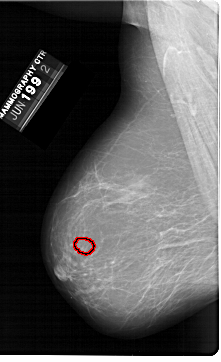

A_1398_1.RIGHT_MLO

RIGHT_MLO LINES 6871 PIXELS_PER_LINE 4021 BITS_PER_PIXEL 12 RESOLUTION 43.5 NON_OVERLAY